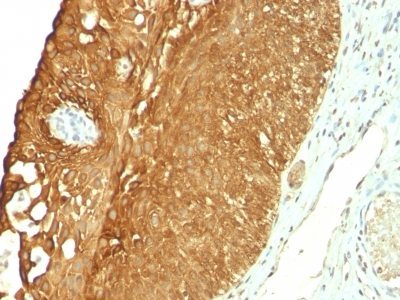

Recognizes a protein of 40 kDa, identified as cytokeratin-19 (CK19), which is expressed in sweat gland, mammary gland ductal and secretory cells, bile ducts, gastrointestinal tract, bladder urothelium, oral epithelia, esophagus, and ectocervical epithelium. Anti-CK19 reacts with a wide variety of epithelial malignancies including adenocarcinomas of the colon, stomach, pancreas, biliary tract, liver, and breast. Perhaps the most useful application is the identification of thyroid carcinoma of the papillary type, although 50%-60% of follicular carcinomas are also labeled. Anti-CK19 is a useful marker for detection of tumor cells in lymph nodes, peripheral blood, bone marrow and breast cancer.